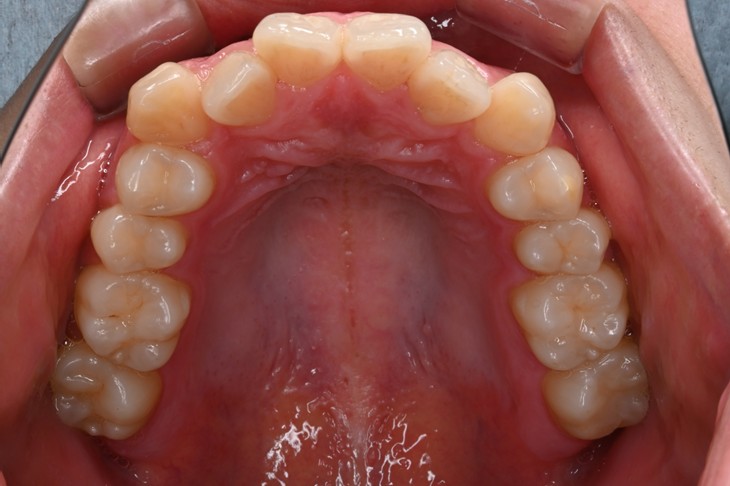

症例2:八重歯が気になる

| 患者様データ | 20代 女性 |

| 来院主訴 | 八重歯が気になる。 |

| 治療内容 | 八重歯を治すために上の親知らずを抜歯し、インビザラインにてマウスピース矯正を開始しました。かみ合わせを整えるためにゴムかけを行いました。 |

| 概算治療費 | 約85万円 |

| 治療期間 | 1年3ヶ月 |

| 通院回数 | 8回 |